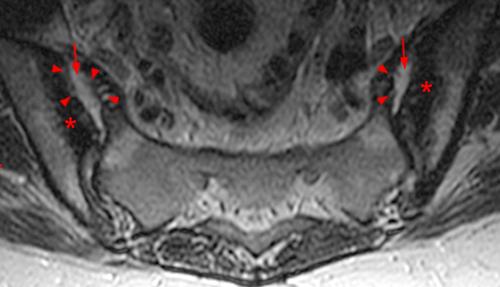

Magnetic resonance imaging has proved useful for visualising inflammation in the sij. The si joints are located at the base of the spine, where the spine joins the pelvis. Other joints can be affected as well.

The disease causes inflammation of the spine and large joints, resulting in stiffness and pain. Involvement of the spine and sacroiliac (si) joints, peripheral joints, digits, entheses are characteristic of the disease. Ankylosing spondylitis frequently attacks the sacroiliac structure as one of its preliminary anatomical targets.

Ankylosing spondylitis (as) inflames the sacroiliac joints located between the base of the spine and pelvis. Ankylosing spondylitis (as) usually affects the spine, but other joints in the body can also be affected. Sacroiliac spondylitis is an inflammatory, autoimmune form of arthritis that can cause big problems in the si joint.